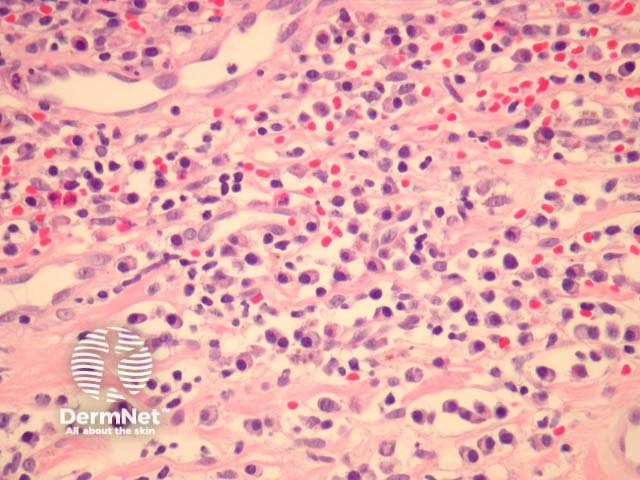

In Zoon balanitis/vulvitis, sections show mucosa which may be attenuated or eroded overlying a dense stromal infiltrate (figures 1,2). The infiltrate contains numerous plasma cells which often form sheets. There may be fewer eosinophils and neutrophils. Vascular ectasia and extravasated erythrocytes are common (figures 1,2,3).

Figure 3